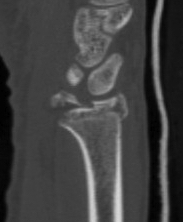

Xray

Dorsal radiocarpal dislocation with dorsal rim fracture

Dorsal radiocarpal dislocation with radial styloid fracture

CT

Radial styloid + dorsal rim fractures